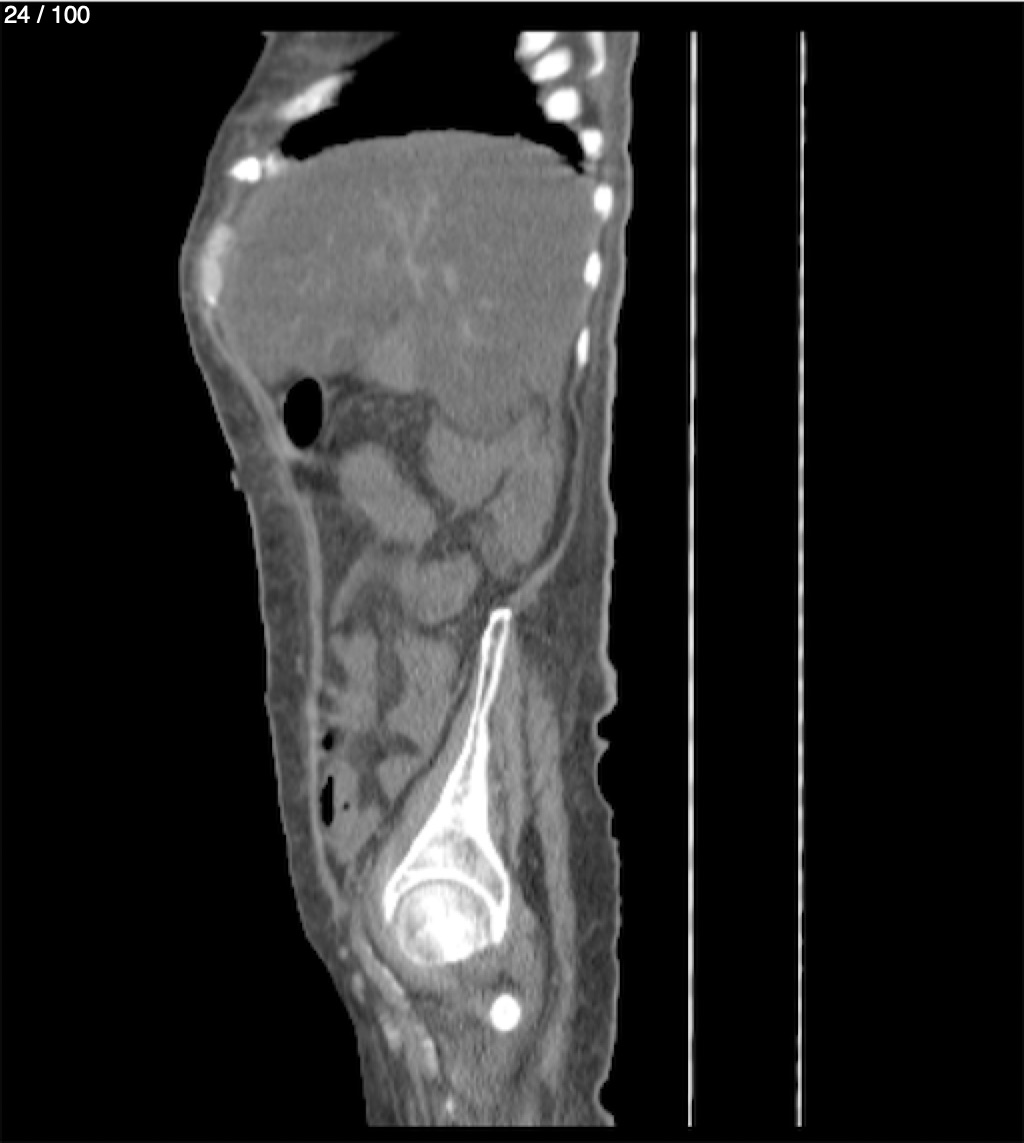

Hilda Geronimo Mendez 60A - T.C Abdomen Simple